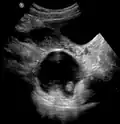

A complex cyst due to a dermoid as seen on ultrasound A complex cyst due to a dermoid as seen on ultrasound